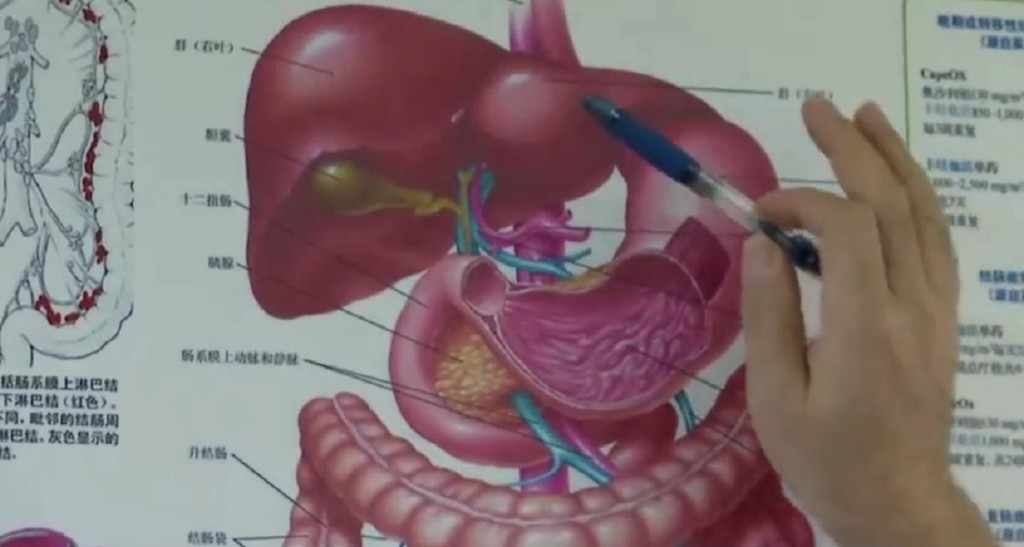

邱磊表示,男子曾罹患結腸癌,當時手術切除掉部分的膈肌(diaphragm),「但修補的部位沒有天生的那麼堅固」,患者經常健身,加上愛喝酒常嘔吐,腹腔壓力變化大,造成膈肌破裂,「長達2米的小腸就從破裂的位置鑽進胸腔」,形成醫學上的「橫膈疝氣」(diaphragmatic hernia,膈疝)。

由於小腸的擠壓,男子左邊的肺已經被頂到嚴重萎縮,小腸堆積充血的結果也導致壞死與內出血,最後經過緊急手術切除,才脫離險境,但原本長約6米的小腸,只剩下約4米。